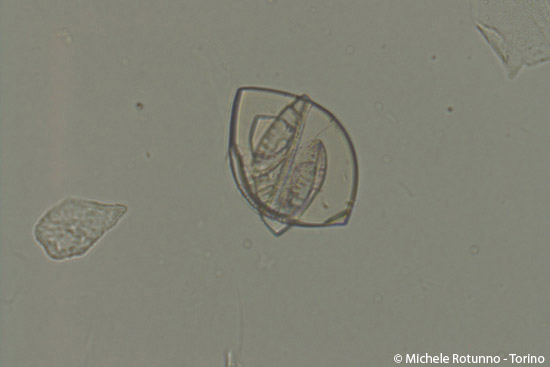

(400x - campo chiaro) - Cristalli di cistina. E’ evidente in questa immagine, oltre alla sovrapposizione derivante verosimilmente da fenomeni di cristallizzazione con apposizione, la fragilità di questi cristalli, i cui margini appaiono qui frastagliati.